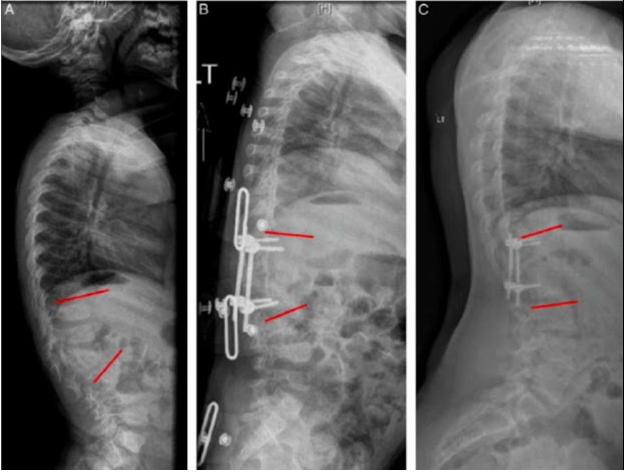

Un nuevo estudio en JPO muestra que la fusión posterior del segmento corto en pacientes muy jóvenes con cifosis congénita puede proporcionar un crecimiento guiado durante años después de la cirugía.

Rocos B, Lebel DE, Zeller R. Congenital Kyphosis: Progressive Correction With an Instrumented Posterior Epiphysiodesis: A Preliminary Report. J Pediatr Orthop. 2021 Mar 1;41(3):133-137. doi: 10.1097/BPO.0000000000001745. PMID: 33448725.